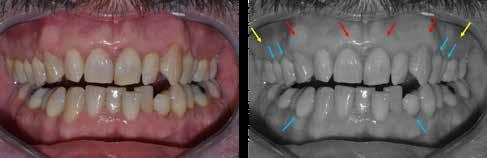

A fogászati kezelések során manapság már nem kizárólag az esztétikai megjelenés helyreállítására törekszünk. Sokszor a kedvezőtlen esztétikai megjelenés hátterében álló okok következményes módon a fogazat funkcionális működését is károsítják, így a kezelések során ezeknek a helyreállításával is foglalkoznunk kell. A különböző funkcionális és esztétikai diszkrepanciák kezelésére számtalan módszer létezik, ám ezen fogászati beavatkozások mindegyikében közös, hogy a kivitelezésük során nagyon szoros együttműködésre van szükség a kezelést végző fogorvos és a munkáját segítő fogtechnikus között. Az alábbi esetbemutatás során egy fiatal hölgypáciens fogazatának héjak alkalmazásával történő esztétikai és funkcionális rehabilitációját szeretnénk ismertetni.

A 19 éves hölgypáciens azzal a kéréssel jelentkezett a rendelőnkbe, hogy szebb fogakat szeretne. Az első konzultáció alkalmával megkérdeztük, hogy mi zavarja leginkább a fogazatának jelenlegi megjelenésében, valamint azt is megbeszéltük vele, hogy milyen végeredmény elérése esetén lenne maradéktalanul elégedett. Ebben az esetben a kezelési célokat az alábbiakban határoztuk meg:

A páciens fogazata esztétikai megjelenésének és funkcionális működésének a lehető legtöbb, saját foganyag megtartása mellett történő helyreállítása (1. és 3. ábra).

A kezelés megtervezése során kifejezett jelentősége van annak, hogy jó kommunikáció legyen a páciens, a fogorvos és a fogtechnikus között. A páciens leendő fogazatának természetes megjelenését a kezelésben részt vevő team szakmai felkészültsége, gyakorlati tapasztalata és a kezelés sikerességének irányába történő elkötelezettsége biztosítja. A beavatkozások megkezdése előtt megtörtént a páciens anamnézisének a felvétele, valamint a klinikai kivizsgálását is elvégeztük. Ezt követően lenyomatokat készítettünk a kiindulási állapotról, majd a kiindulási helyzetet extra- és intraorális fotók segítségével is rögzítettük (13. a-c. ábra).